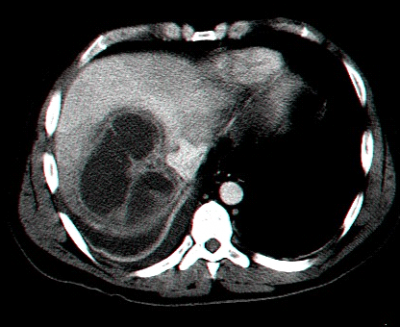

בטומוגרפיה ממוחשבת ניתן לראות מילוי של חומר ניגוד בהמנגיומה (תצלומים 15.10-17.10).

- בטומוגרפיה ממוחשבת ניתן לראות גוש בכבד (תצלום 25.10).

| תצלום 25.10: ציסטות מרובות בכבד. מימין הציסטות הן חלק ממחלה פוליציסטית מערכתית. משמאל ציסטות המוגבלות לכבד בלבד. | |